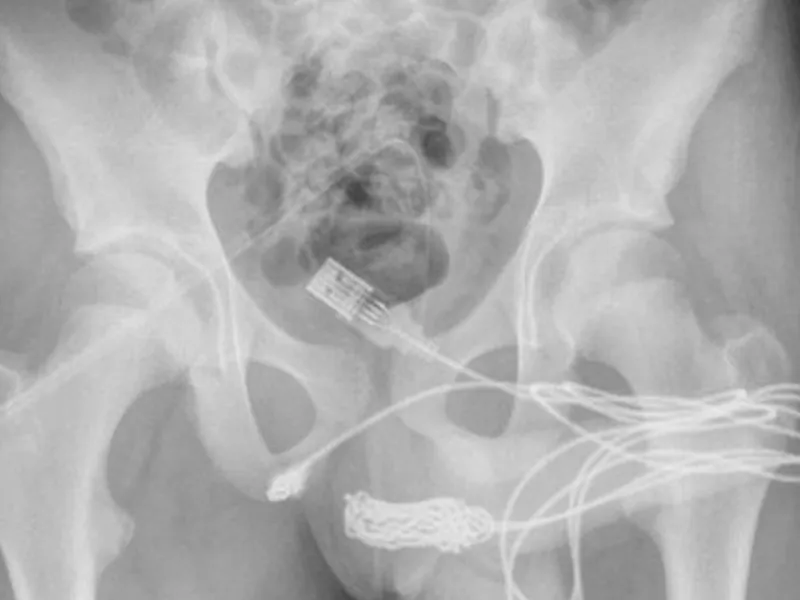

Medicii au scris: "S-a constatat că cele două porturi distale ale cablului USB ieșeau din meatul uretral extern, în timp ce partea din mijloc a cablului înnodat a rămas în interiorul uretrei.

"S-a făcut o incizie longitudinală peno-scrotală peste corpul străin palpabil și s-a efectuat o disecție atentă prin țesuturile mai profunde, despicând mușchiul bulbospongios.

"Ambele capete ale firului au fost scoase cu succes prin meatul uretral extern".

Medicii au folosit o tijă metalică pentru a scoate cablul, dar nodurile au dovedit că acest lucru este imposibil.

Într-un final, medicii au fost nevoiți să taie secțiunea dintre organele genitale și anus pentru a putea ajunge la cablu de dedesubt.